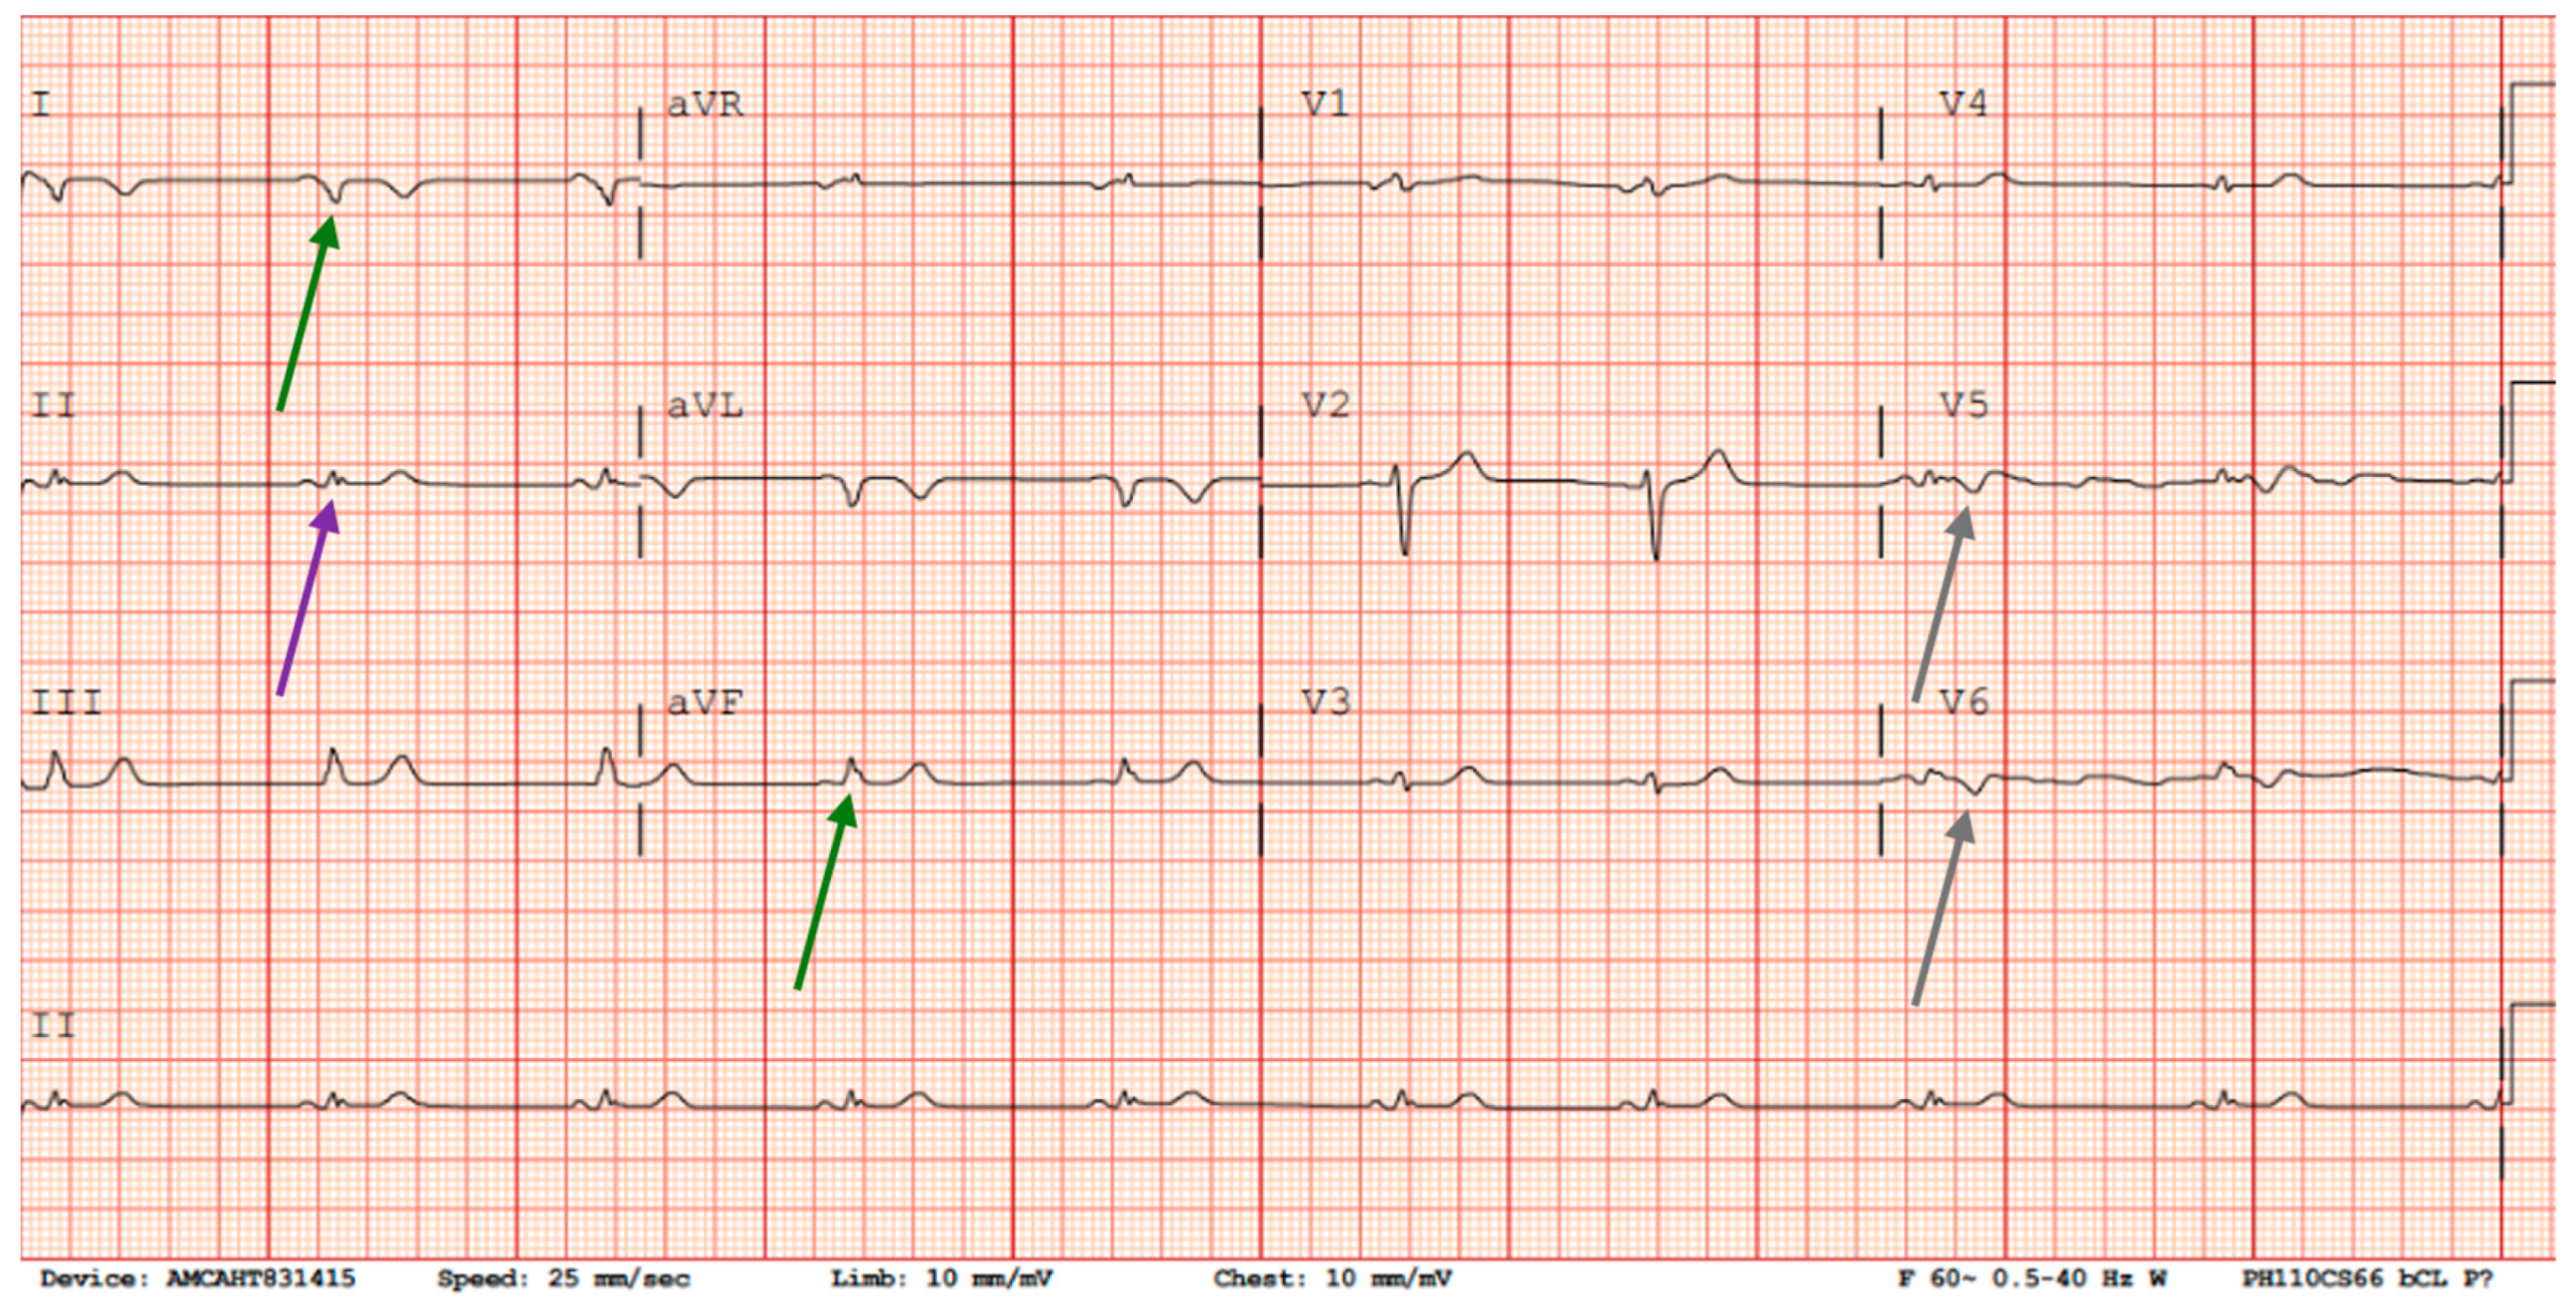

She was premedicated with diphenhydramine 50 mg PO and acetaminophen 650 mg, and the infusion of 250 mg was run at 50 mL/hour for 37 min. During the second infusion, chest tightness recurred within 30 min after starting. An ECG showed right axis deviation, abnormal T waves in the lateral leads, and a decrease in overall voltage compared to the ECG 5 days prior. Troponin levels rose to 164 ng/L before trending down to 146 ng/L 4 h later (Figure 3). No repeat echocardiogram or catheterization was performed, as her symptoms resolved following discontinuation of the infusion. The recurrence of symptoms and biomarker elevation strongly implicated rituximab as the trigger for both the initial and subsequent cardiac events.

At a 50 mL/hr rate, the patient again developed chest pain, this time within the first 30 min of infusion. ECG now showed new T-wave inversions in lead V5 and lowered QRS voltage in limb leads. Troponin increased to 164 ng/L, then trended down to 146 ng/L within 4 h, consistent with reinfarction or myocardial injury. No hemodynamic instability was noted.

Figure 3. ECG after the second rituximab infusion with right axis deviation (II and aVF, green arrows), low voltage in extremity leads (II, purple arrow), abnormal T waves in lateral leads (V5 and V6, gray arrows), and overall lower voltage from EKG 5 days prior.